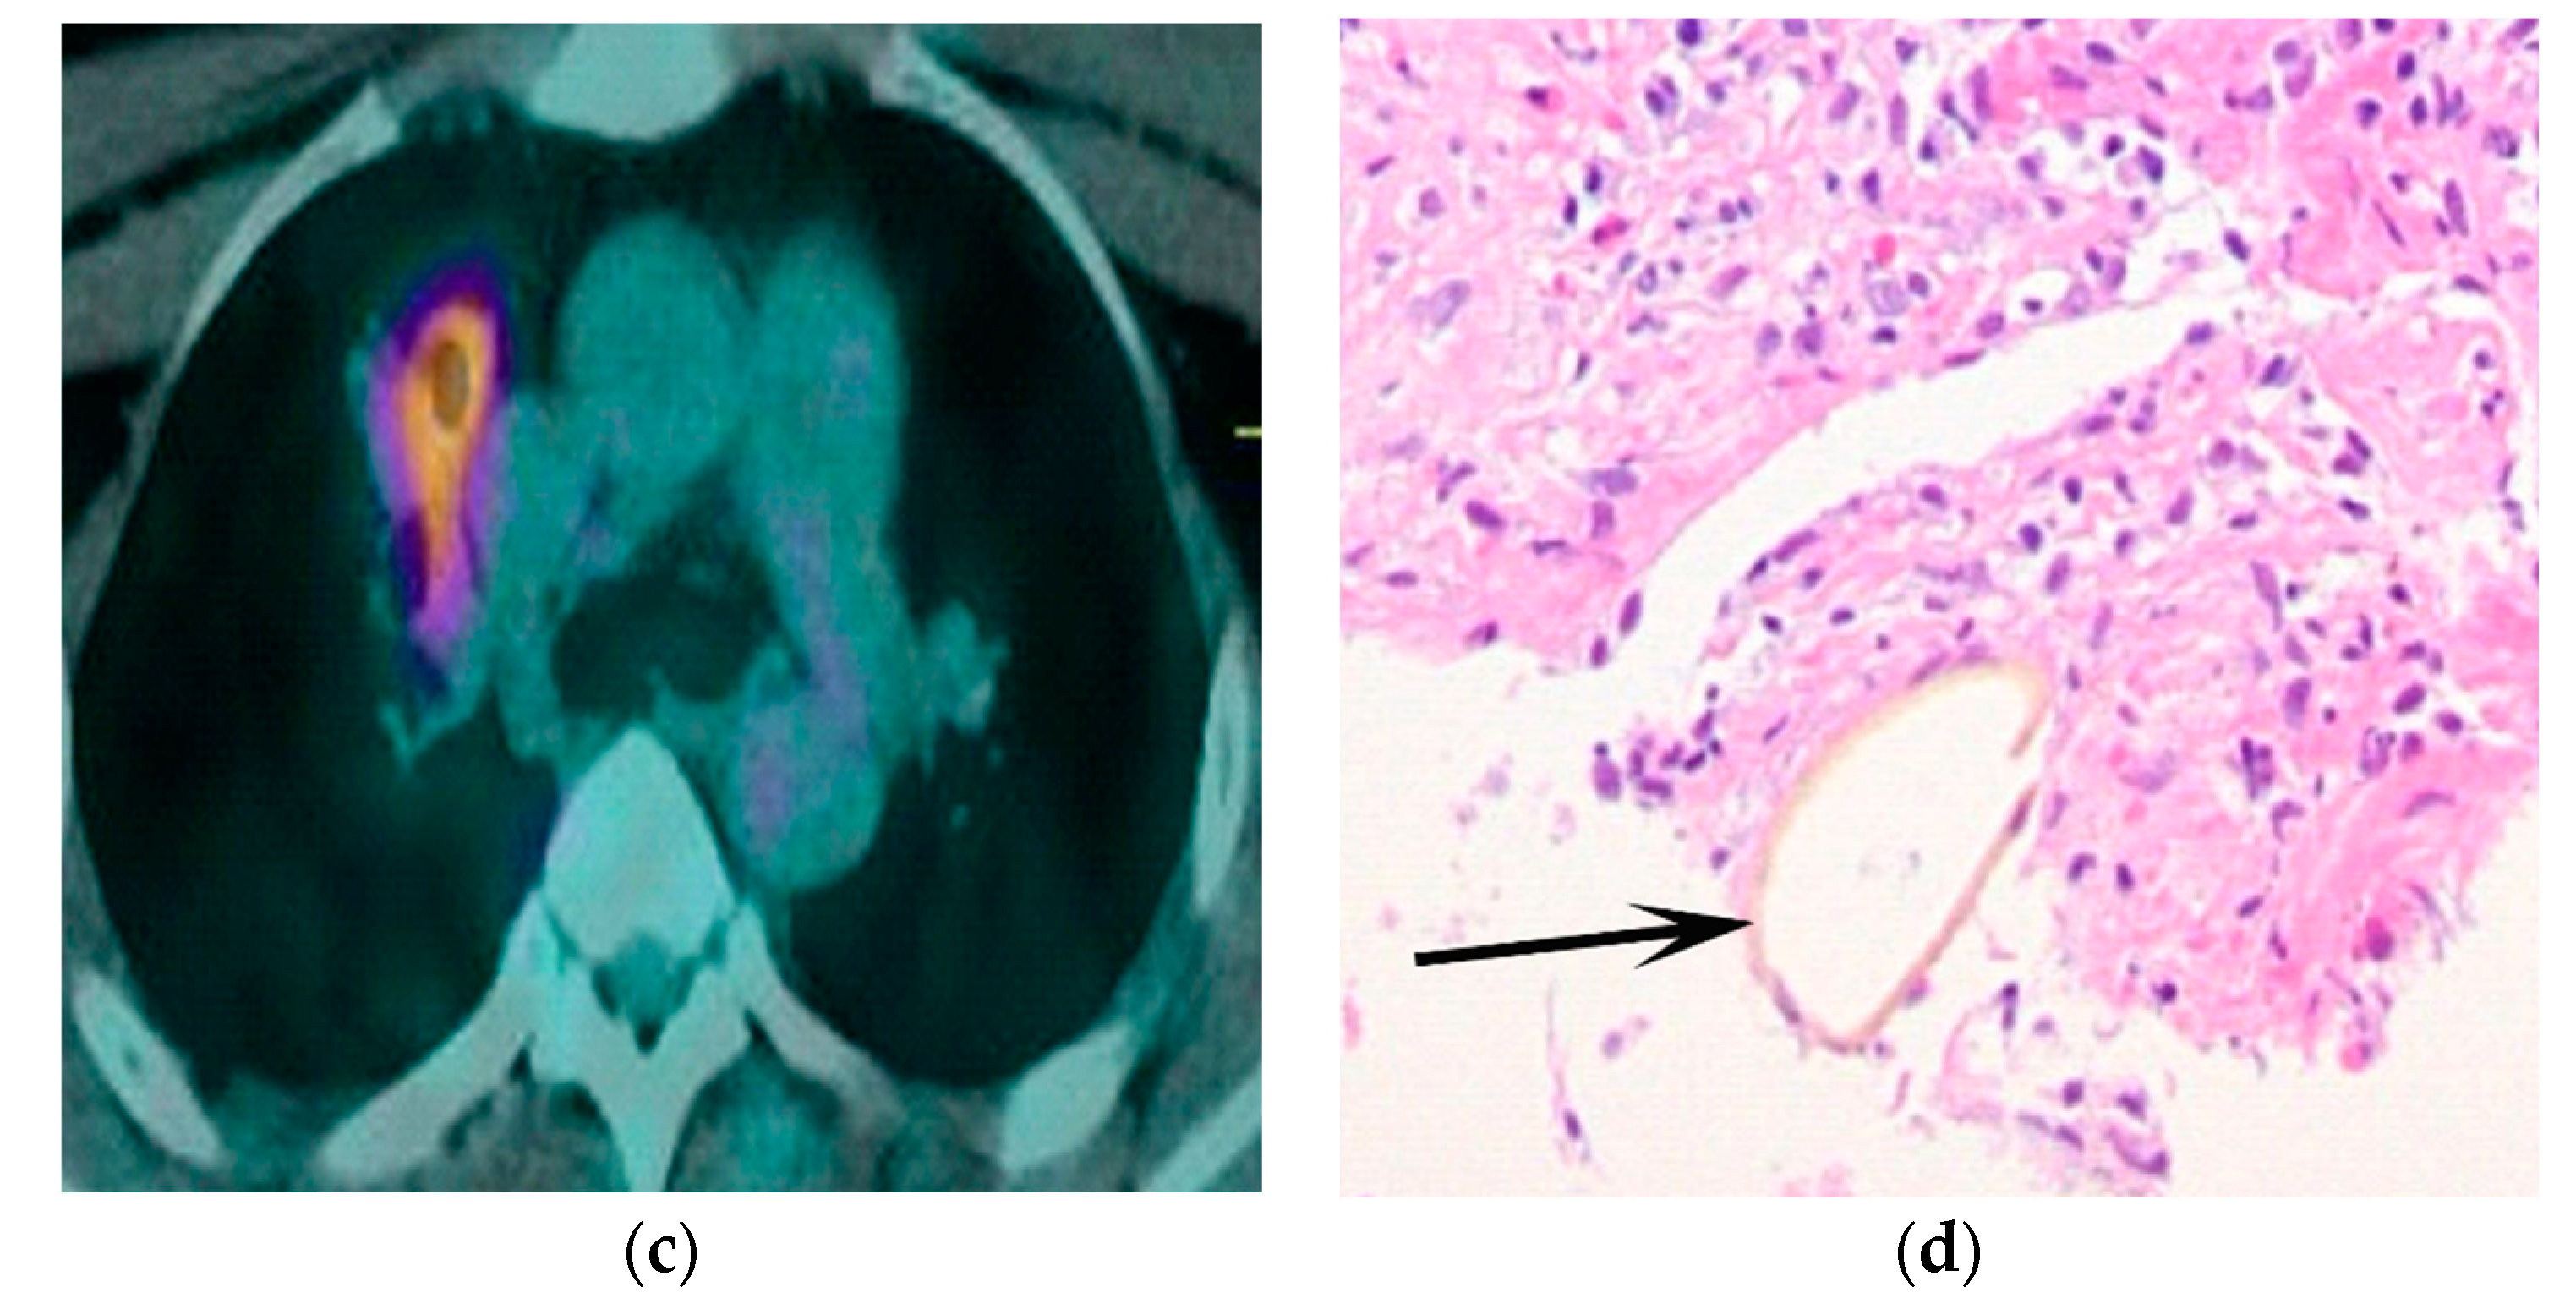

What Findings on Chest CTs Can Delay Diagnosis of Pleuropulmonary Paragonimiasis?

- Kim, T.S.; Han, J.; Shim, S.S.; Jeon, K.; Koh, W.-J.; Lee, I.; Lee, K.S.; Kwon, O.J. Pleuropulmonary paragonimiasis: CT findings in 31 patients. AJR. Am. J. Roentgenol. 2005, 185, 616–621. [Google Scholar] [CrossRef]

- Song, J.U.; Um, S.W.; Koh, W.J.; Suh, G.Y.; Chung, M.P.; Kim, H.; Kwon, O.J.; Jeon, K. Pulmonary paragonimiasis mimicking lung cancer in a tertiary referral centre in Korea. Int. J. Tuberc. Lung Dis. Off. J. Int. Union Against Tuberc. Lung Dis. 2011, 15, 674–679. [Google Scholar] [CrossRef] [PubMed]

- Shu, Q.-H.; Yang, Y.; Li, S.-D.; Zhao, J.-S.; Li, S.-H.; Wang, M.-M.; Wang, W.-Q.; Tian, M.; He, S.-M.-Q.; Ma, Z.-Q.; et al. Analysis of the misdiagnosis of 8 adult cases of paragonimiasis with lung masses as the main manifestation in Xishuangbanna, Yunnan. J. Cardiothorac. Surg. 2021, 16, 28. [Google Scholar] [CrossRef] [PubMed]